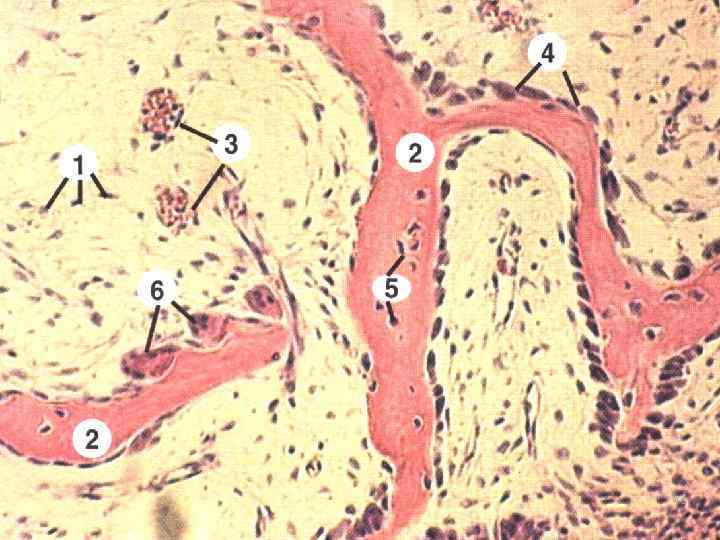

Структура грубоволокнистой костной ткани: наглядные примеры